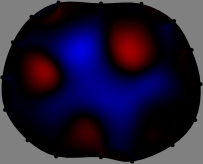

To explain the FER method, we closely examine the correlations among column vectors of the sensitivity matrix , described in Fig. 2. The correlation between and can be expressed as

for [23]. This shows that the column vector is like an EEG (electroencephalography) data induced by dipole sources with directions at locations . Given that two dipole sources at distant locations produce mutually independent data, the correlation between and decreases with the distance between and . Fig. 2 shows a few images of the correlation as a function of for four different positions . The correlation decreases rapidly as the distance increases. In the green regions where the correlation is almost zero, is nearly orthogonal to .

Fig. 2 shows that if and are far from each other, the corresponding columns of the sensitivity matrix are nearly orthogonal. This somewhat orthogonal structure of the sensitivity matrix motivates an algebraic formula that directly computes the local ensemble average of conductivity changes at each point using the inner product between changes in the data and a scaled sensitivity vector at that point: